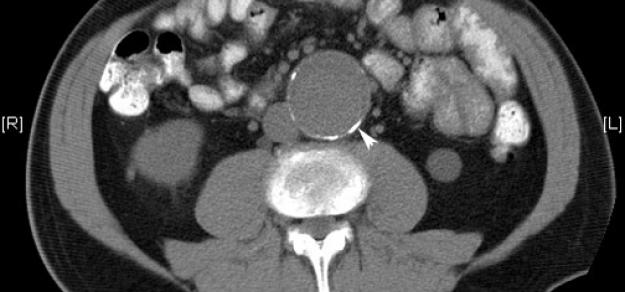

Lancet, 22 de mayo de 2019  Estos resultados excluyen todo, excepto un aumento muy modesto en el riesgo de hemorragia intracerebral recurrente con terapia antiplaquetaria en pacientes en terapia antitrombótica para la prevención de la enfermedad vascular oclusiva cuando desarrollaron hemorragia intracerebral. El riesgo de hemorragia intracerebral recurrente es probablemente demasiado pequeño para exceder los beneficios establecidos de la terapia antiplaquetaria para la prevención secundaria.

Frecuencia de hemorragia intracraneal con aspirina a dosis baja en individuos sin enfermedad cardiovascular sintomática

JAMA Neurol, 13 de mayo de 2019   se asoció con un mayor riesgo general de hemorragia intracraneal y un mayor riesgo de hemorragia intracerebral para las personas de raza / etnia asiática o personas con un índice de masa corporal bajo.